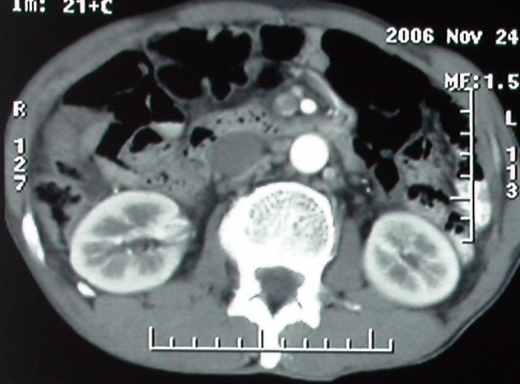

增强ct所见

门脉主干及肠系膜上静脉近端明显增粗,尤其前者呈等低混杂密度,增强后周围见轻度环形强化。明显占位效应。肝内外胆管见大量气体影。胆囊明显增大。

影像表现:胆囊扩张、肝内胆管不扩张,且见肝脏内树枝样气体影;十二指肠后方等密度占位,中心有不规则囊变区。增强实质部分轻度强化。下部腔静脉未强化------有栓子吗?

1、胰头部占位:胰管轻度扩张(可疑双管征),主要考虑恶性肿瘤,胰头癌?十二指肠间质瘤?后腹膜肿瘤?

2、门静脉高压症,主要考虑胰头部肿块压迫或者浸润所致肝前性门静脉主干受压;肝功能尚可,脾脏不大,无脾亢;

3、胆囊积液、肝胆管积气、胆道扩张伴有胆道感染;

ct表现:1,胰腺钩突后方肿块,不均强化,中心密度低,钩突及门静脉前移。2:肝右后叶不均强化灶,突出肝表面,3:胆囊明显增大,肝内胆管及肝总管内积气。4:腹腔内少量积液。

胆囊扩张、肝内胆管不扩张,且见肝脏内气体影;十二指肠后方等密度占位,中心有不规则囊变区。增强实质部分强化。下部腔静脉未强化------有栓子吗?

胰头后方肿块,周边强化,胰头受压推移,肝脏右后叶异常强化灶,首先考虑肝癌后腹膜淋巴结转移;2、肝内胆管积气。